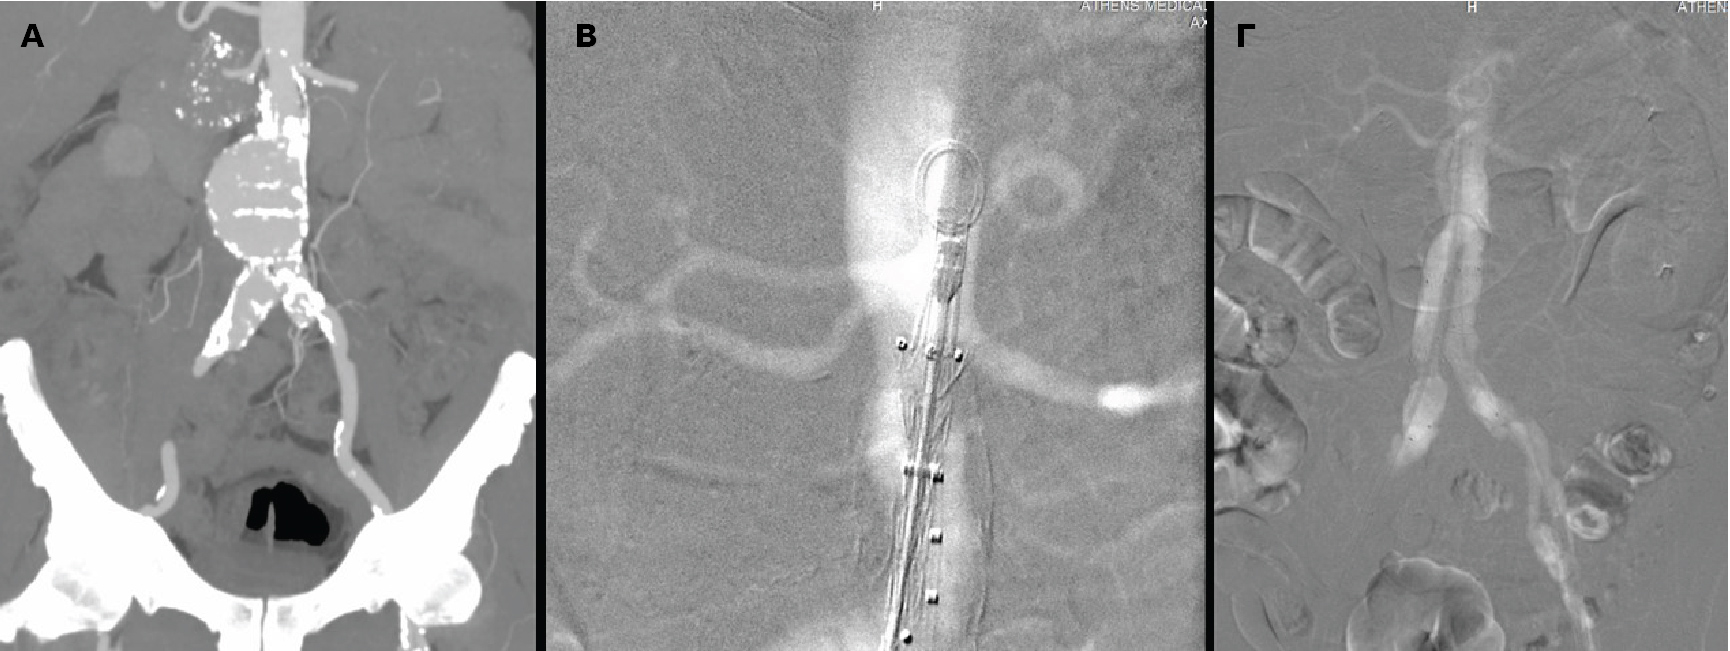

Α. Προεγχειρητική αξονική αγγειογραφία του ανευρύσματος της κοιλιακής αορτής, B. Διεγχειρητική αγγειογραφία με διοξείδιο του άνθρακα για την ακριβή έκπτυξη του μοσχεύματος κάτω από τις νεφρικές αρτηρίες, Γ. Τελική διεγχειρητική αγγειογραφία με διοξείδιο του άνθρακα, που επιβεβαιώνει την επιτυχή ενδοαυλική αποκατάσταση του ανευρύσματος |

Η ενδαγγειακή αντιμετώπιση αορτικών ανευρυσμάτων έχει αντικαταστήσει, σχεδόν πλήρως, την ανοιχτή χειρουργική εξαιτίας της ελάχιστης επεμβατικότητας της μεθόδου, της γρήγορης ανάρρωσης του ασθενούς και της ασφάλειας των σύγχρονων μοσχευμάτων. Η τεχνική απαιτεί όμως, τη χρήση ιωδιούχου σκιαγραφικού, στο πλαίσιο της αγγειογραφίας, για την απεικόνιση των αγγείων πριν και μετά την τοποθέτηση των μοσχευμάτων. Η ποσότητα του σκιαγραφικού που χρησιμοποιείται είναι ανάλογη της πολυπλοκότητας του ανευρύσματος. Επιπρόσθετα, ο ασθενής λαμβάνει επιπλέον ιωδιούχο σκιαγραφικό κατά τη διάρκεια της αξονικής αγγειογραφίας που είναι απαραίτητη πριν την επέμβαση αλλά και μετεγχειρητικά, ιδιαίτερα σε πολύπλοκα αορτικά ανευρύσματα.

Αξίζει να σημειωθεί ότι η ποιότητα της αγγειογραφίας ήταν ισάξια με αυτήν του ιωδιούχου σκιαγραφικού, τα μοσχεύματα τοποθετήθηκαν με απόλυτη επιτυχία αποκλείοντας το ανεύρυσμα και η νεφρική λειτουργία του νεφροπαθούς ασθενούς δεν επηρεάστηκε καθόλου.